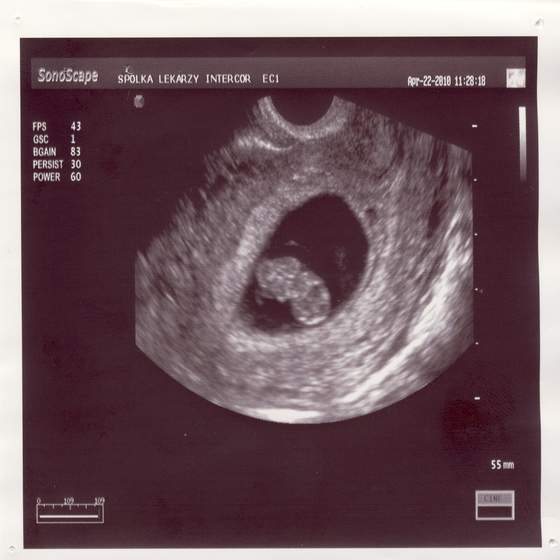

Byłam wczoraj u ginka i załączam Wam zdjatko małej 2 cm fasolinyjak widziałam bijące serduszko to się popłakałam....Zobacz załącznik 238861

piękne maleństwo och kiedy u mnie się takie cudo zagnieździ :-(